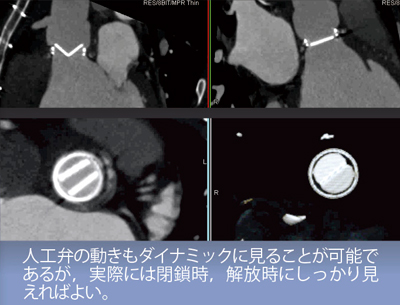

人工弁は,置換後に機能不全に陥っていないかを評価することが重要である。人工弁の部分に血栓やパンヌス(結合組織)が付着することで,弁に開放制限が出て機能不全を起こす。

人工弁の開放角は,一葉弁のBejork Shileyは60°,二葉弁のSt. Jude Medicalは85°,Carbomedicsは78°と決まっているため,人工弁の角度を計測することで機能不全を診断できる。

人工弁の動きは,CTで非常に明瞭に観察することができる(図6)。動きをダイナミックに見ることも可能であるが,開放角の測定には,閉鎖時と開放時をしっかりと観察できればよく,特に,図6のような開放時に,鮮明かつアーチファクトの少ない画像が重要となる。

図6 大動脈弁の描出(開放角の測定)